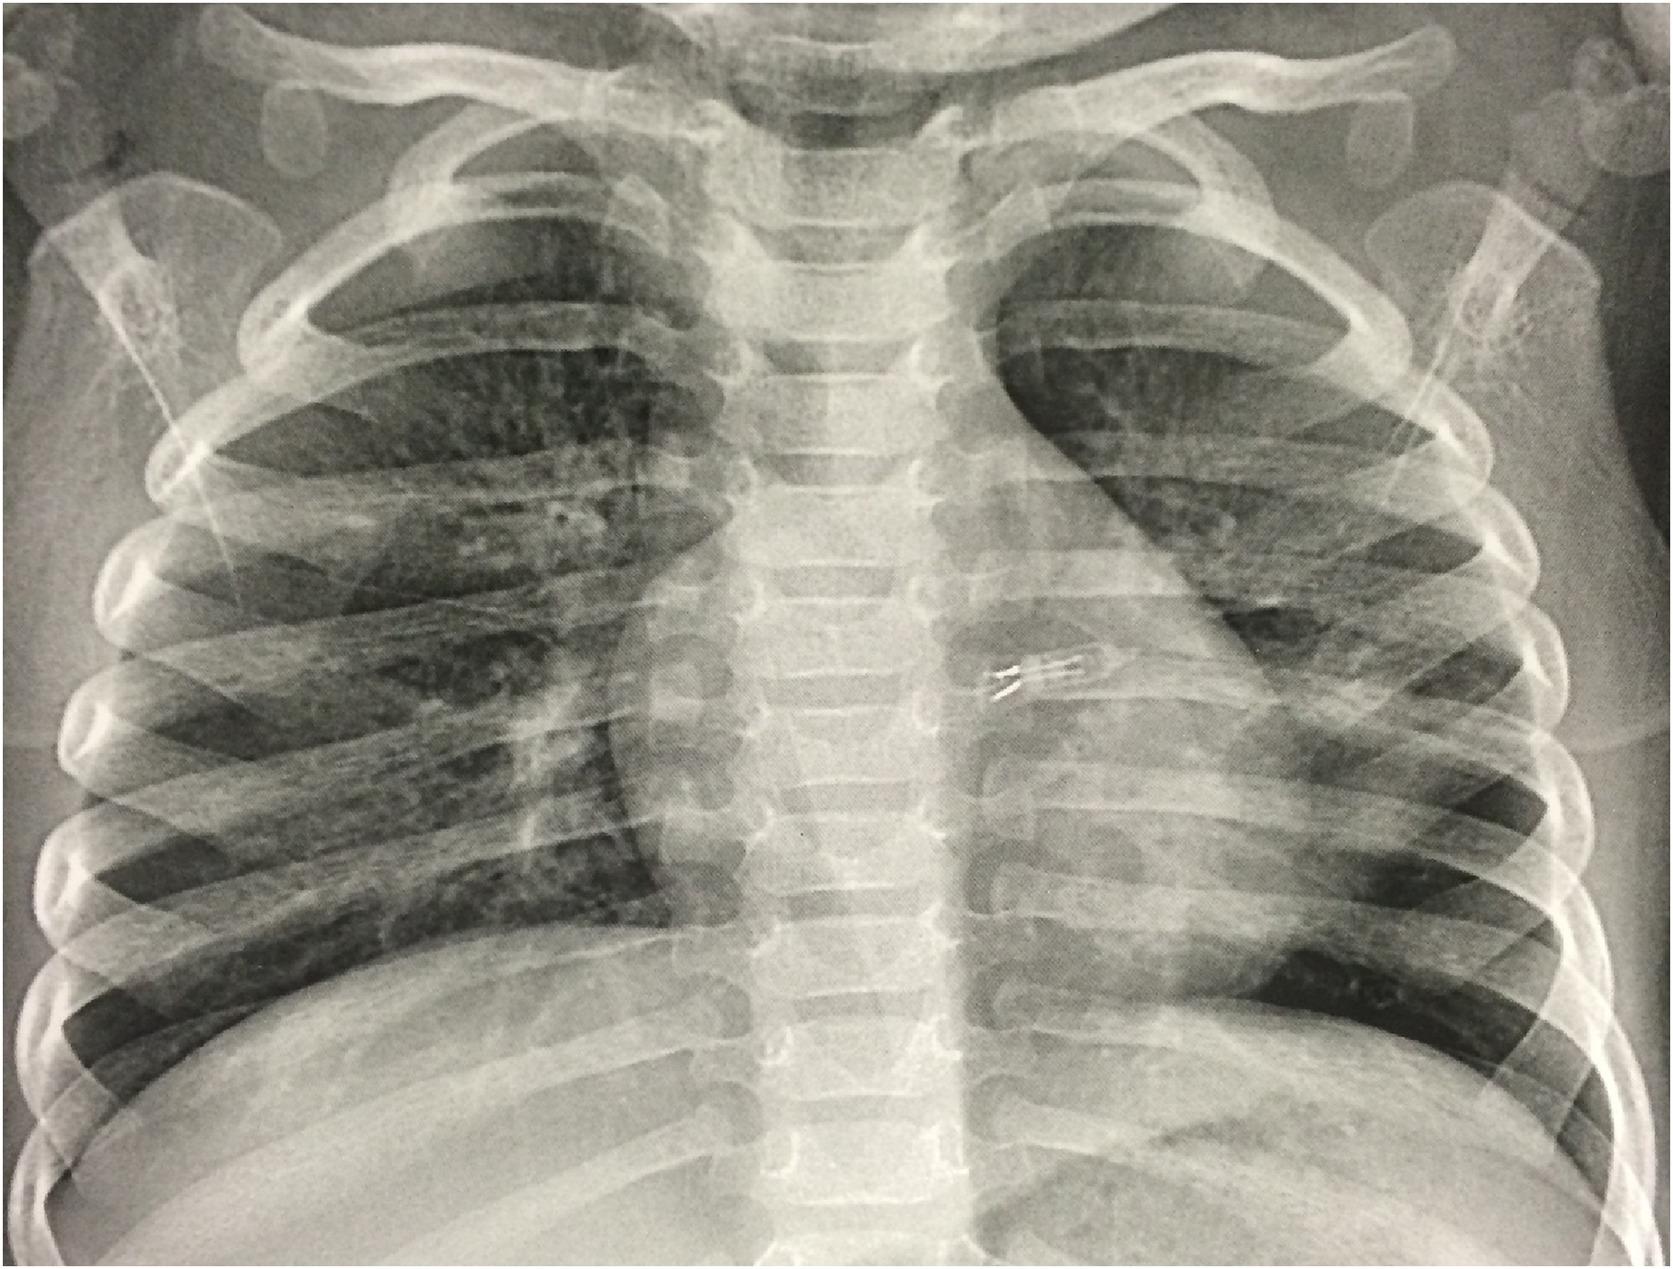

Elle passe une radiographie pulmonaire auprès des médecins du service de pneumologie pédiatrique. Et là, c’est la surprise : les images révèlent un objet en forme de U qui s’est logé dans la bronche gauche. Les internes comprennent alors que l'objet est en réalité une ampoule de guirlande lumineuse ! Et qu’elle est à l'origine des problèmes respiratoires de la petite.